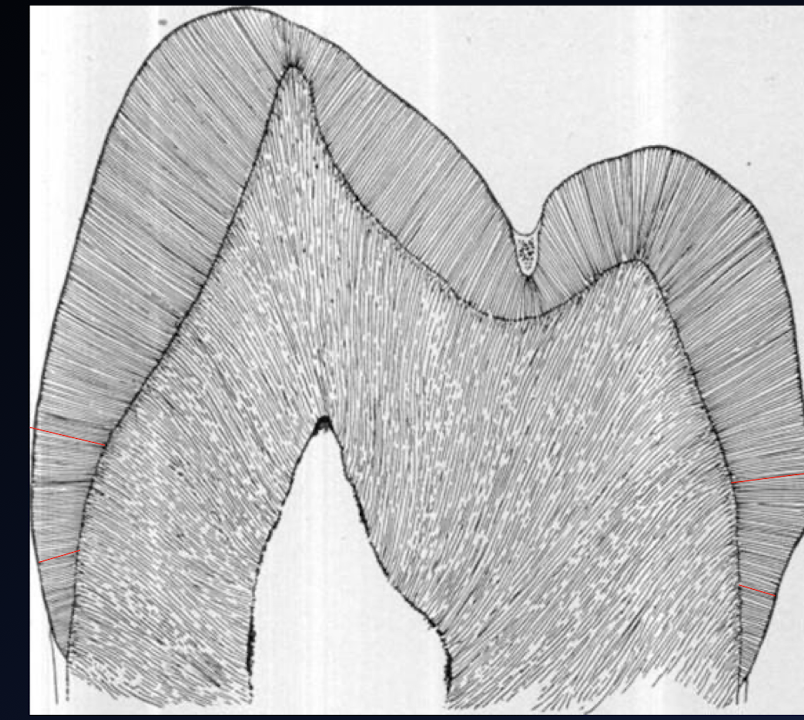

enamel rods

All external walls are __ to the external tooth structure, thereby _ the enamel rods

Follows the contour of the ?

__ mesio-distally, leaves dentin bulk for ?

Roughly __ to external tooth surface occluso-gingivally

orientation of walls

All four walls must meet the cavosurface at __ degrees

All walls will __ from axial wall to the cavosurface

convex, pulp protection

parallel

90 degrees

Diverge

__ internal line angles

__ axial wall follows ? (?)

Mesial, distal, gingival, and incisal walls ___ to enamel rods and perpendicular to external tooth surface (slight divergence)

smooth, curvature of tooth, (convex)

Parallel